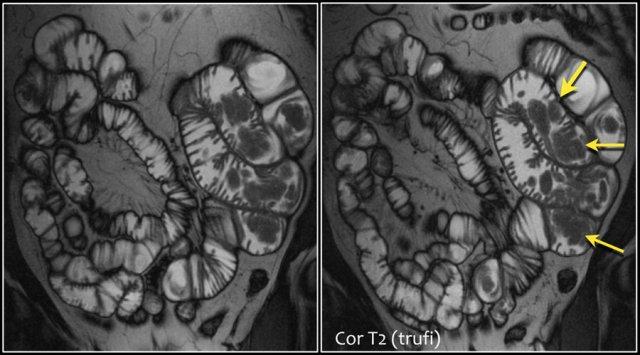

Các dấu hiệu ghi nhận được:

- Hình ảnh đảo ngược nếp gấp niêm mạc gợi ý bệnh celiac

- Lồng ruột hồi-hồi tràng (mũi tên vàng), ở bệnh nhân u lympho ruột non đa ổ (không phải tất cả các tổn thương đều được thể hiện ở đây).

- Hạch bạch huyết mạc treo to (mũi tên đỏ).

EATL

Đây là một bệnh nhân khác mắc bệnh celiac.

Có một khối không đều tại hỗng tràng kèm giãn lòng ruột.

Có hình ảnh thâm nhiễm mạc treo.

Kết quả giải phẫu bệnh cho thấy u lympho tế bào T trong bệnh celiac.

Đây được gọi là u lympho tế bào T liên quan đến bệnh lý ruột (Enteropathy-Associated T-cell Lymphoma – EATL).

Đây là một loại u lympho tế bào T ảnh hưởng đến ruột non ở bệnh nhân mắc bệnh celiac.

Đây là một ví dụ khác về u lympho tế bào T trong bệnh celiac.